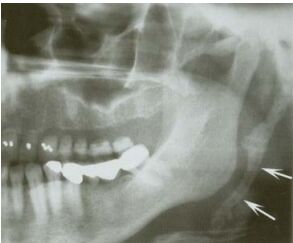

75.下圖為部分顎全景 X 光影像,箭頭所指處為下列何者? (A) 頸椎(cervical vertebrae)之影像 (B) 鈣化之莖突舌骨韌帶(stylohyoid ligament) (C) 對側下顎骨後緣之複影 (D) 攝影時患者手指摸頸部所致